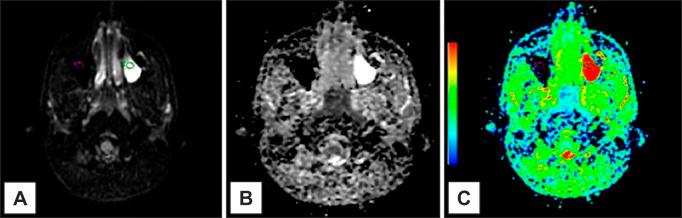

The cases reported were: presence of air-fluid levels, mucosal thickening and a mucous retention cyst. Conventional magnetic resonance imaging and apparent diffusion coefficient (ADC) maps, with ADC values were demonstrated. In the literature review, the studies considering inflammatory lesions were detailed, as well as ADC values established by investigators.

ADC values for presence of air-fluid levels, mucosal thickening and mucous retention cyst were respectively: 1.99 x 10 mm/s; 1.83 x 10 mm/s; 2.05 x 10 mm/s.

气液平面、黏膜增厚和黏液潴留囊肿的ADC值分别为:1.99×10⁻³mm²/s;1.83×10⁻³mm²/s;2.05×10⁻³mm²/s。